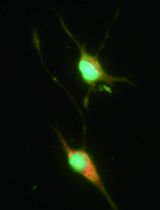

Cover of Journal of Virology, featuring study using the protocol.